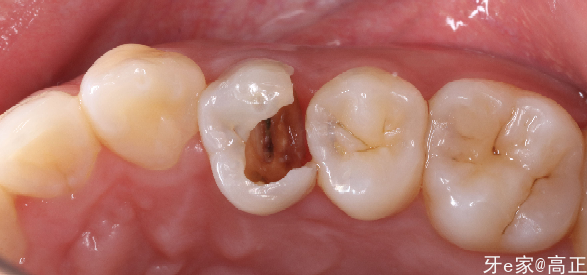

口腔检查:右上4大面积龋坏,可见食物嵌塞,冷诊无反应,叩( -),探(-),黏膜颜色无异常

辅助检查:龋坏穿髓,余无异常

诊断:右上4残冠

右上4牙髓坏死